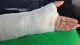

@ChiquiVigo Escayolada. Pesa como un niño muerto. Hay que moverla con tino porque tiene unas agujas que la cruzan y salen fuera que joden que no veas... y da calor y pica. Nada que no arreglen unos chop sticks y mucha paciencia, supongo... aunque Jode saber que lunes empezaban mis vacaciones me iba a ir de playita y calderetas a Menorca

@Pafman 4 meses de escayola y férula por un hueso que llevaba 20 años roto sin avisarme, bajo amenaza de perder toda la movilidad de la muñeca

Tras remover Roma con Santiago encontré a un tipo dispuesto a intentar otra cosa, la reconstrucción, con un injerto de hueso y unos clavos y un postoperatorio largo... y que me daba no más de un 40% de posibilidades de éxito. Hace hoy un año me levantaba de una noche en blanco entre dolores insoportables después de someterme a esa intervención, sin mucha esperanza de que sirviese para algo. Pasé 5 meses con escayola, luego férula, y revisiones cada mes que eran un "bueno, algo parece que se pega, pero va muy despacio, no creo que llegue a consolidar, vamos a darle un poco más de tiempo a ver....". A finales de año me dieron el alta, aún con dudas, y hoy tengo una mano casi plenamente funcional.

Luego bajó la marea, empezamos a espaciar los chutes y a moverme y me mandaron a casita con mi mano chunga y mi tajo de 8 cms en la cadera. Mi estómago dice que todo esto muy mal y ha reventado, para darle alegría a la cosa, pero ya me visto casi sola y camino, ayudo a hacer la cena, pequeñas cosas.

He visto mi mano, con sus piercings forzosos. Pude rascarme algunos costrones de piel y sentir agua correr por ella... La musculatura menguante, el color blanquecino, vello oscuro saliendo donde nunca lo hubo (¿por la cirugía?¿me pasaron una cuchilla?) Tenía una forma extraña, parecía de otra persona o ser Me mareé un poquito mientras la miraba atónita esperando la radiografía. Pero mola saber que sigue ahí debajo